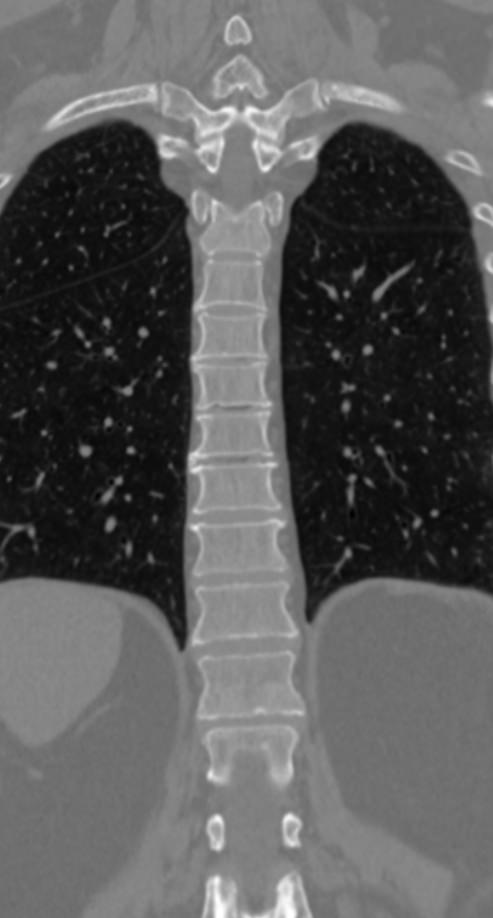

Мультиспиральная компьютерная томография (МСКТ) является современным, высокоинформативным методом диагностики различной патологии позвоночного столба. Благодаря МСКТ можно визуализировать костную структуру позвонков, выявить воспалительные, дегенеративные и опухолевые процессы на исследуемом уровне. В основе метода лежит использование ионизирующего излучения и способность различных тканей по-разному поглощать рентгеновские лучи.

В нашей клинике КТ двух отделов позвоночника проводится на новейших мультиспиральных томографах экспертного уровня TOSHIBA AQUILION (64-срезовый и 128-срезовый). Сканеры производят тончайшие срезы исследуемой зоны толщиной от 0,5 мм и позволяют визуализировать костные структуры позвоночника с высокой детализацией. Увеличенное количество высокочувствительных детекторов аппаратов обеспечивает высокую разрешающую способность и четкость изображений, при этом позволяет выполнить исследование в течение нескольких секунд с минимальной дозой облучения.

Инновационные возможности мультиспиральных томографов, которыми оснащены наши медицинские центры, позволяют создавать 3D-модели позвоночника на рассматриваемом уровне для более точной локализации очага и оценки взаимного расположения органов и тканей.

Комплексное обследование двух отделов позвоночника показано при подозрении на множественное поражение различных отделов позвоночного столба, которые могут быть обусловлены развитием опухоли, метастатическим поражением, воспалительными или дегенеративными заболеваниями.